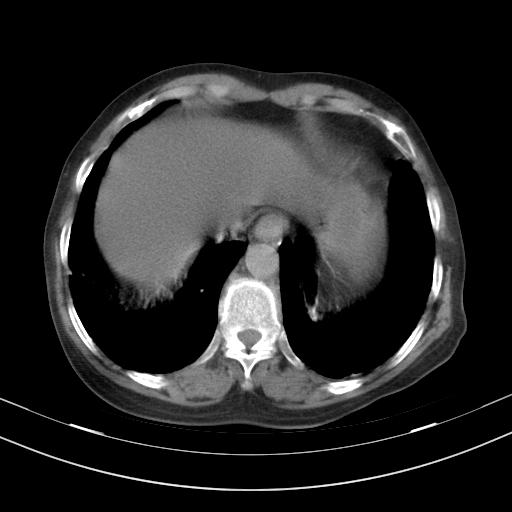

老年女性,嗜睡3天,意识模糊。轻咳,无发热。

两肺慢支炎伴感染,左侧胸腔积液。纵膈及双侧肺门淋巴结肿大建议复查。

1)两肺感染性病变;建议抗炎治疗后复查。2)纵隔淋巴结肿大。3)左侧胸腔积液。

3)左侧胸腔积液。